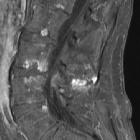

MRI

May demonstrate interspinous bursal fluid and posterocentral epidural cyst(s). MRI can be very helpful in determining whether there is resulting posterior compression of the thecal sac.